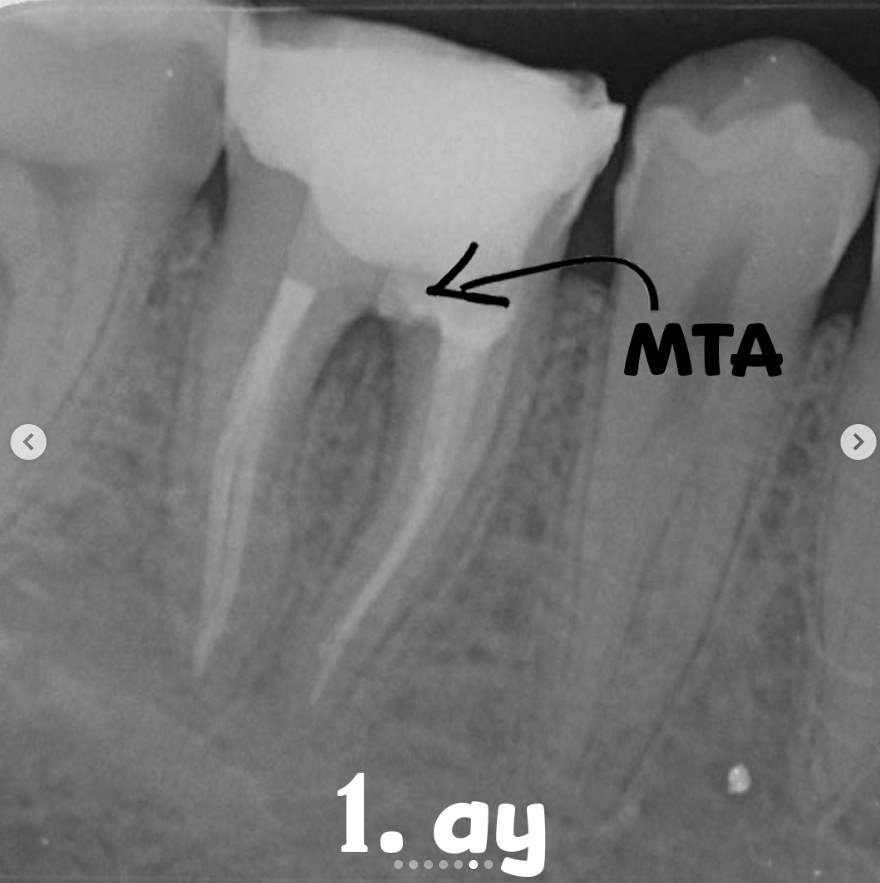

• Following necessary arrangements at the perforation site, it was sealed with MTA, and a moist cotton pellet was placed for 15 minutes to allow initial setting.

At the 1-month recall, healing of the sinus tract was observed, and the tooth was found to be functioning well intraorally.

No adverse clinical findings were detected.